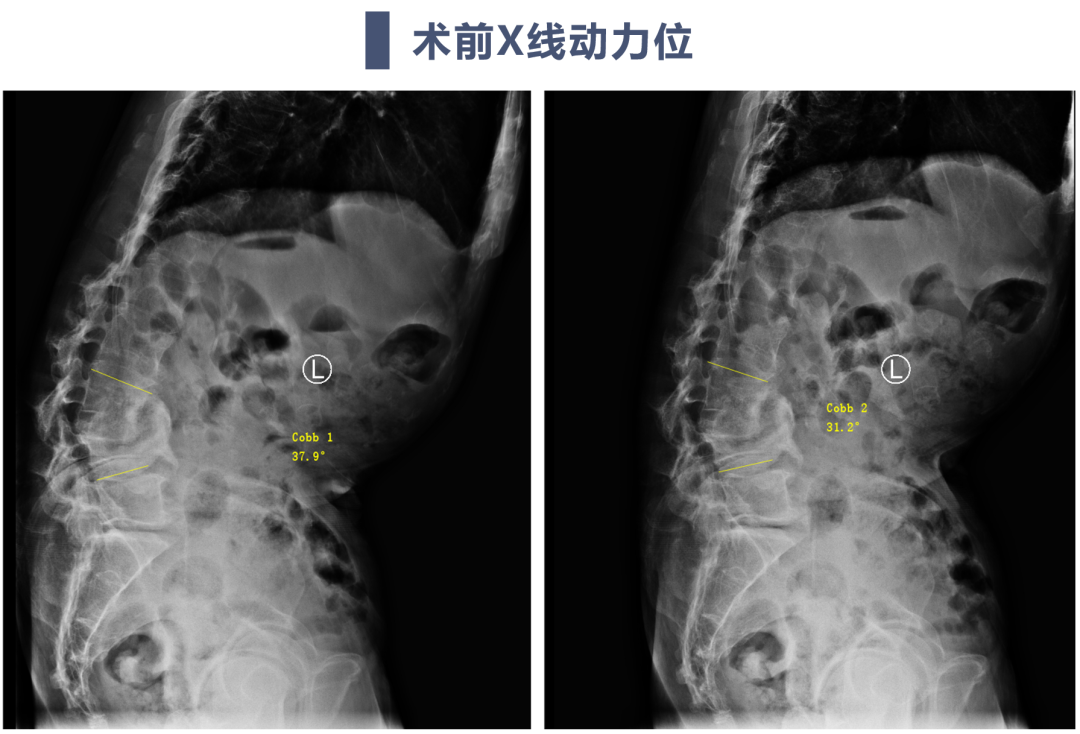

讨论主题:L4压缩骨折伴脊柱侧后凸畸形

影像资料:

腰椎侧后凸畸形

腰椎陈旧性压缩性骨折(L4)